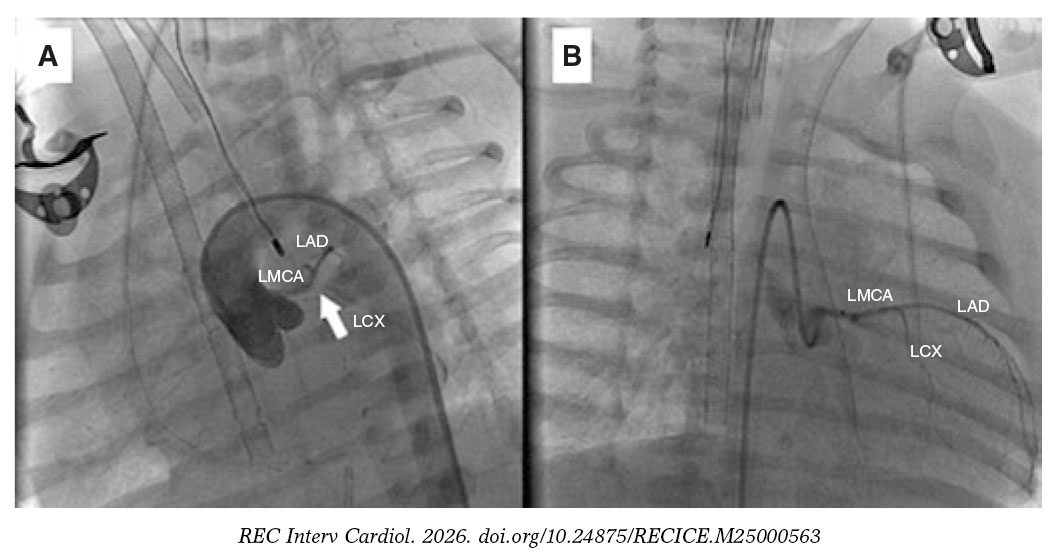

Due to hemodynamic instability despite intubation and vasoactive support, we performed cannulation for extracorporeal membrane oxygenation and cardiac catheterization to rule out coronary artery disease. A normal origin of the left coronary artery was found, with lack of contrast opacification at the junction of the left anterior descending (LAD) and left circumflex (LCX) coronary arteries, and slow distal filling of both vessels (figure 2A and video S3 and video S4; LMCA, left main coronary artery). We performed local fibrinolysis using a microcatheter with administration of 2 boluses of alteplase (0.8 mg and 0.4 mg), achieving recanalization of the LCX and the origin of the LAD (figure 2B).

Figure 2.